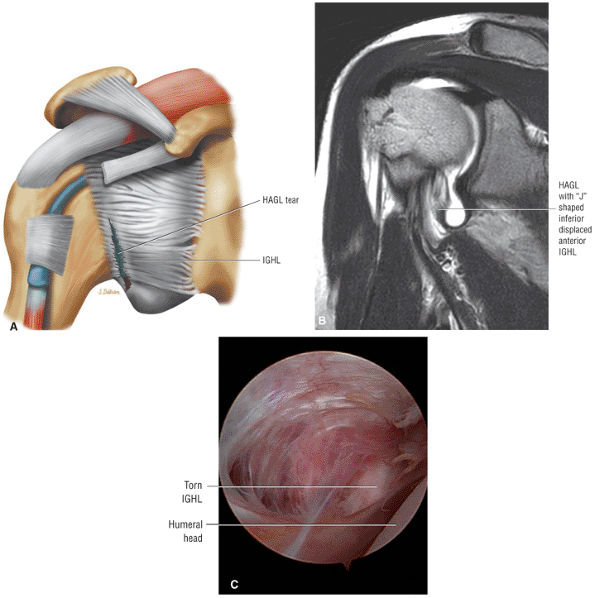

-

Rotator cuff tendinosis is most conspicuous on FS PD FSE images. It does not demonstrate hyperintensity on T2 FSE images. Partial- and full-thickness tears are hyperintense on both FS PD FSE and T2 FSE sequences unless associated with chronic scarring or granulation tissue.

![]() |

|

FIGURE 8.104 ● The subacromial bursa extends over the insertion of the supraspinatus superiorly and over the infraspinatus and teres minor posteriorly. The superior surface of the bursa is in contact with the undersurface of the acromion, the coracoacromial ligament, and the origin of the mid-portion of the deltoid muscle. The superior surface of the bursa extends medially adjacent to the deep surface of the acromioclavicular joint.